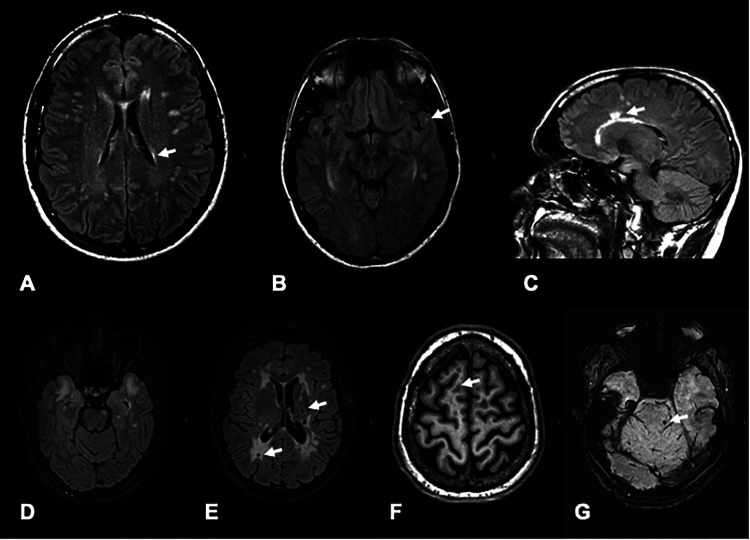

Results: A disease-causing variant in NOTCH3 was identified in one patient without CSF-OCBs, no spinal lesions, with non-response to immunotherapy, and a family history of dementia, thereby converting the diagnosis to cerebral autosomal-dominant arteriopathy with subcortical infarcts and leukoencephalopathy (CADASIL). Moreover, 18 patients (6.5% of total) carried variants of unclear significance.